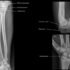

Leg or lower extremity

Femur

Tibia

Fibula